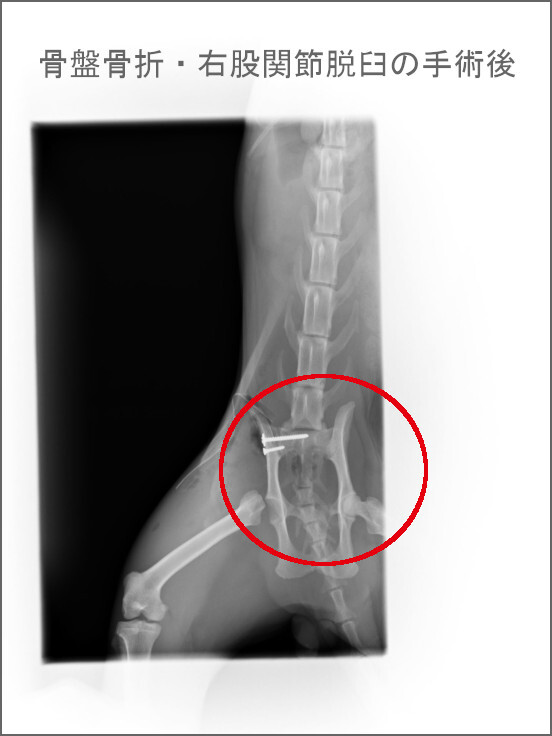

・骨盤骨折

・右股関節脱臼

骨盤の骨折、脱臼の手術のほか、去勢手術も一緒にしてもらいました。

術後のレントゲン撮影